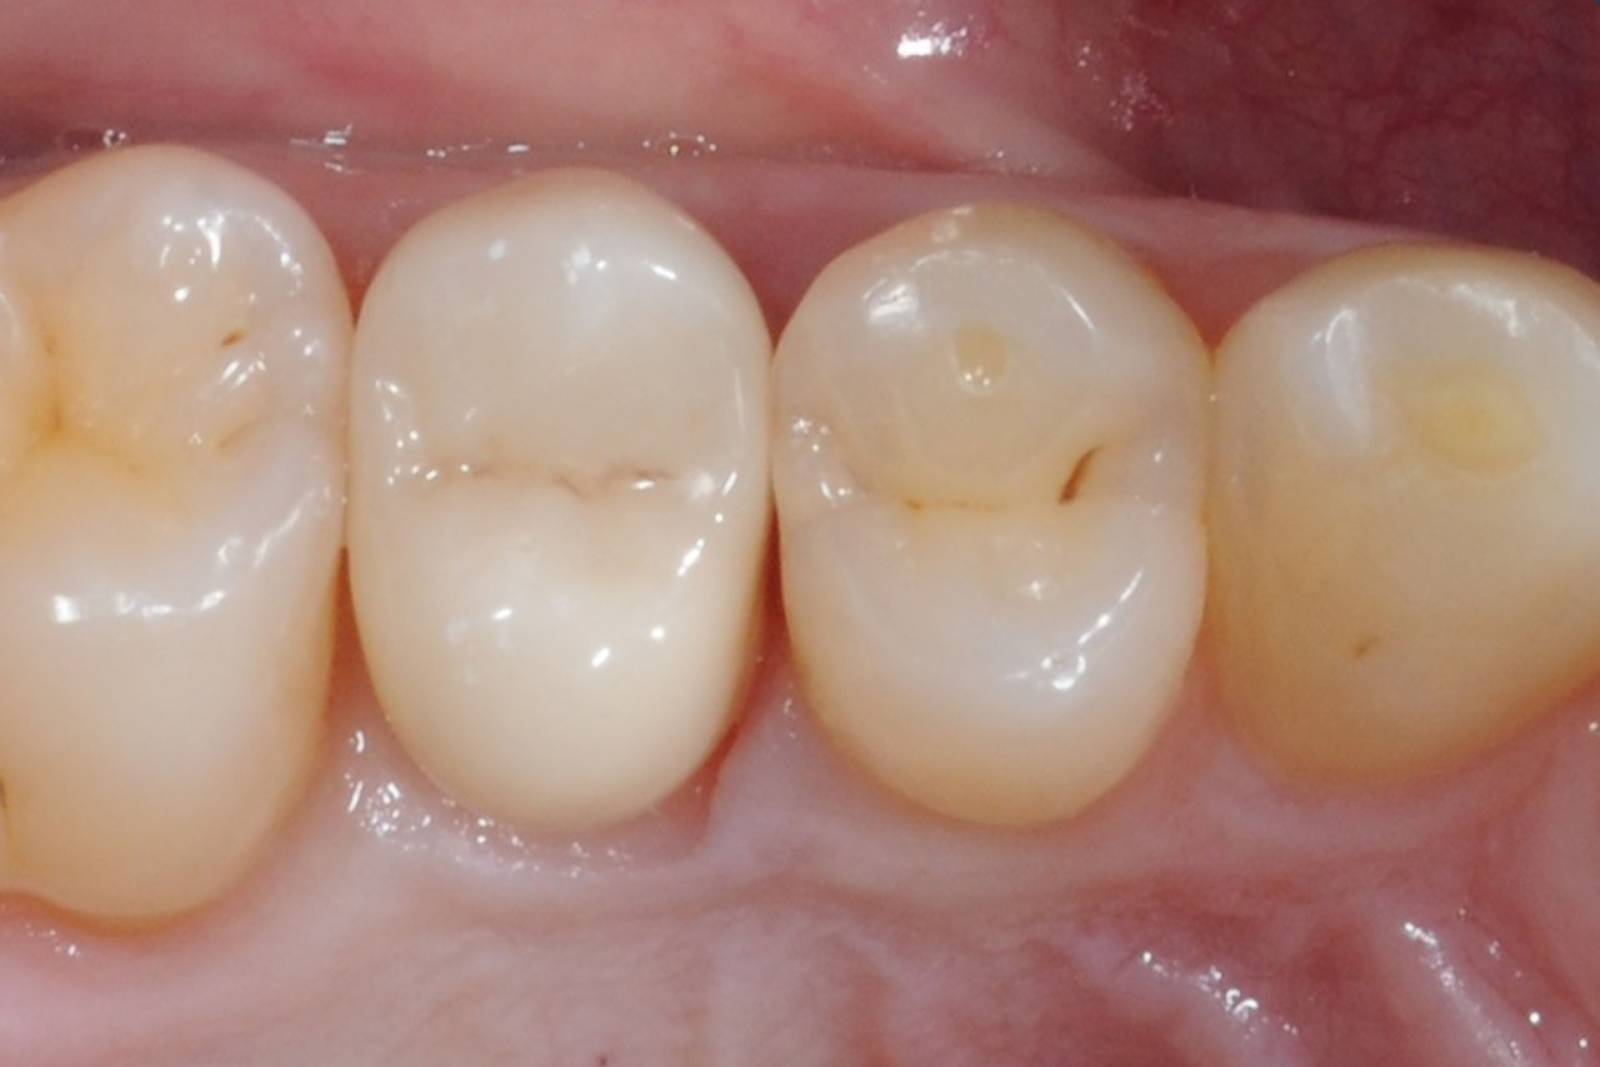

Before

Fractured ceramic restoration made from a leucite-reinforced glass-ceramic after a clinical service time of 12 years.

After

Chairside-fabricated restoration made from an advanced lithium-disilicate ceramic CEREC Tessera.